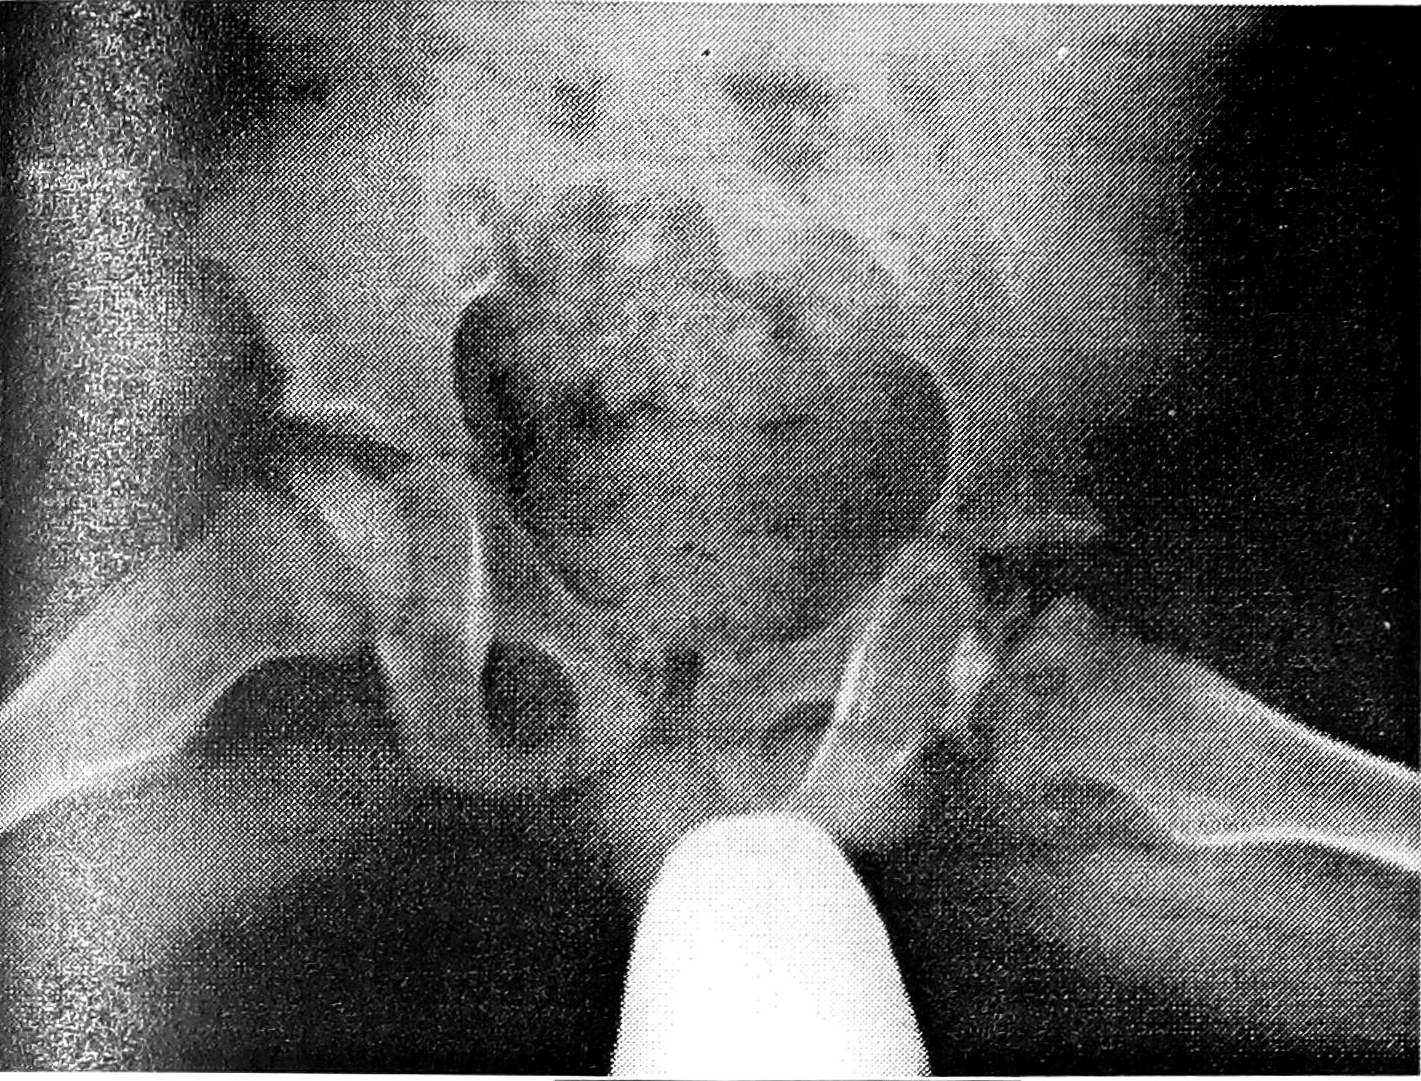

Рис. 2. Больной М. 3 лет. Наблюдается по поводу асептического некроза головки левого бедра.

Справа головка уплощена, с неровными контурами.

При изучении головки бедренной кости (у детей с односторонней БП особое внимание обращали на так называемый «здоровый» сустав) учитывали: наличие остеопороза или остеосклероза, уплощение, характер контуров (гладкие, неровные), структуру (от равномерной до фрагментированной). Типичная картина двустороннего асептического некроза головки бедренной кости выявлена у 11 больных. У 20 пациентов с клиническим диагнозом односторонней БП типичные признаки асептического некроза «здоровой» головки бедра с фрагментацией ее отсутствовали. У 18 из них отмечались: неравномерная структура головки — у 3, незначительное или умеренное уплощение — у 12, остеопороз — у 3, неровные контуры — у 3 (рис. 1 и 2 на вклейке). При динамическом наблюдении на протяжении 2—3 лет эти микросимптомы на «здоровой» стороне у 2 больных развились в типичную картину асептического некроза головки бедренной кости. Лишь у 2 из 20 пациентов изменения выявлялись только с одной стороны: у одного ребенка (12 лет) была типичная картина односторонней БП, у другого (5 лет) изменения ограничивались неравномерностью структуры и неровностью контуров головки бедра.

У 8 пациентов, обратившихся с жалобами на боли в тазобедренных суставах, повышенную утомляемость при ходьбе и наблюдавшихся в поликлинике с подозрением на двустороннюю БП, отмечались незначительные изменения в обеих головках бедер: остеопороз, небольшое уплощение, неровность контуров, неравномерность структуры (рис. 3 на вклейке). У 2 больных при наблюдении в течение соответственно 2 и 3 лет заметного изменения рентгенологической картины не обнаружено.

Рис. 3. Больная К. 7 лет. Клинический диагноз: подозрение на двустороннюю болезнь Пертеса.

Головки бедер с обеих сторон уплощены, справа определяется остеопороз, слева — неравномерная структура головки.